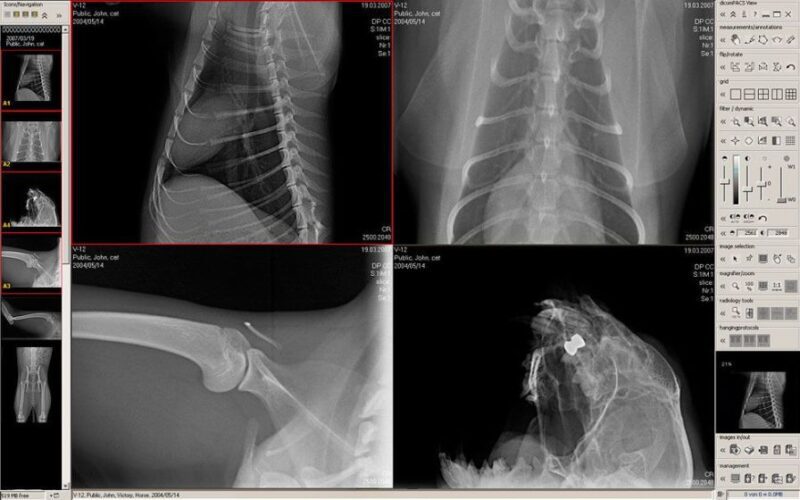

روش های پرتونگاری تخصصی – رادیوگرافی و تکنیک های تخصصی بعد از کشف اشعه اکس توسط رونتگن خیلی زود شروع شد. در آن زمان متوجه شدند که وارد شدن مواد مختلف در ارگان های مختلف بدن باعث نمایش بسیار خوب ویژگی های آناتومیک آن ها می شود. در اوایل سال های ۱۹۰۰ رادیو گرافی تکنیک های تخصصی محدود به نواحی نظیر کیسه صفرا، دستگاه گوارش و دستگاه ادرای بود. با ایجاد و توسعه تکنیک های پیچیده تر، این تکنیک های اولیه به تکنیک های تشخیص روتین با ماده کنتراست تبدیل شدند و در بخش های رادیولوژی مدرن به صورت روزانه انجام می شود.

جزوه پیش رو که توسط یکی از متخصصین این حوزه تهیه شده است در قالب PDF با بیش از ۵۰ اسلاید به همراه تصاویر اختصاصی بصورت کاملا مفصل به روش های پرتونگاری تخصصی می پردازد.